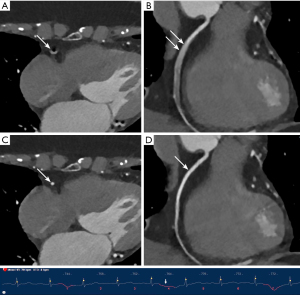

Similarly, the use of MCR significantly improved subjective image quality and interpretability in both subgroups, with a more evident difference observed in the high HR and/or arrythmias group. In the low HR group, although subjective image quality scores performed with MCR displayed a consistent superiority, no significant difference was noted in terms of interpretability by every coronary artery (all P>0.05). Conversely, in the high HR and/or arrythmias group, the application of MCR resulted in a remarkable improvement in interpretability at all levels. Concerning the major three coronary arteries, the greatest benefit in interpretability improvement was found for RCA, where the proportion of arteries considered non-interpretable decreased dramatically from 70.3% to 8.1% (P<0.001). Figures 3-6 display four representative clinical cases, among which Figure 6 contains invasive coronary angiography image.

MCR showed remarkable improvements in subjective image quality and interpretability in the overall population and both subgroups, an observation that was particularly evident for the higher HRs (HR ≥75 bpm), which is consistent with previous research (15,16). Notably, the inclusion criteria of patients with arrhythmia were less strictly controlled in the present study, rendering our study population relatively more representative for an actual clinical scenario. Motion artifacts produced by a constantly beating heart deteriorates the delineation of coronary arteries, especially for patients with AF characterized by high HR and high HR variability, which have traditionally been excluded from CCTA examinations (32,33). However, CCTA with the application of MCR achieved sufficient image quality, tremendously reducing the ratio of segments deemed non-interpretable from 30.0% to 1.9% in the high HR and/or arrythmias group.

Analysis by segments revealed that the mid-segment of the RCA yielded the lowest image quality because it is perpendicular to the scanning plane leading to the most severe motion artifacts (34). As a result, the greatest benefit from MCR was obtained in this segment. In the low HR group, despite the continuous superiority of subjective image quality scores with the use of MCR across all evaluated segments, there was no significant difference regarding interpretability for every coronary artery. A plausible explanation for this result is that patients with lower HRs are less susceptible to motion artifacts due to possessing having relatively longer diastolic phase of the cardiac cycle, usually referred to as the “cardiac quiescence” phase (35). Consequently, there would be less room for the motion-correction algorithm to enhance image quality. Additionally, the sample size of this subgroup was limited, which might be an important factor contributing to the lack of statistical significance. Therefore, MCR showed limited improvements in this regard.